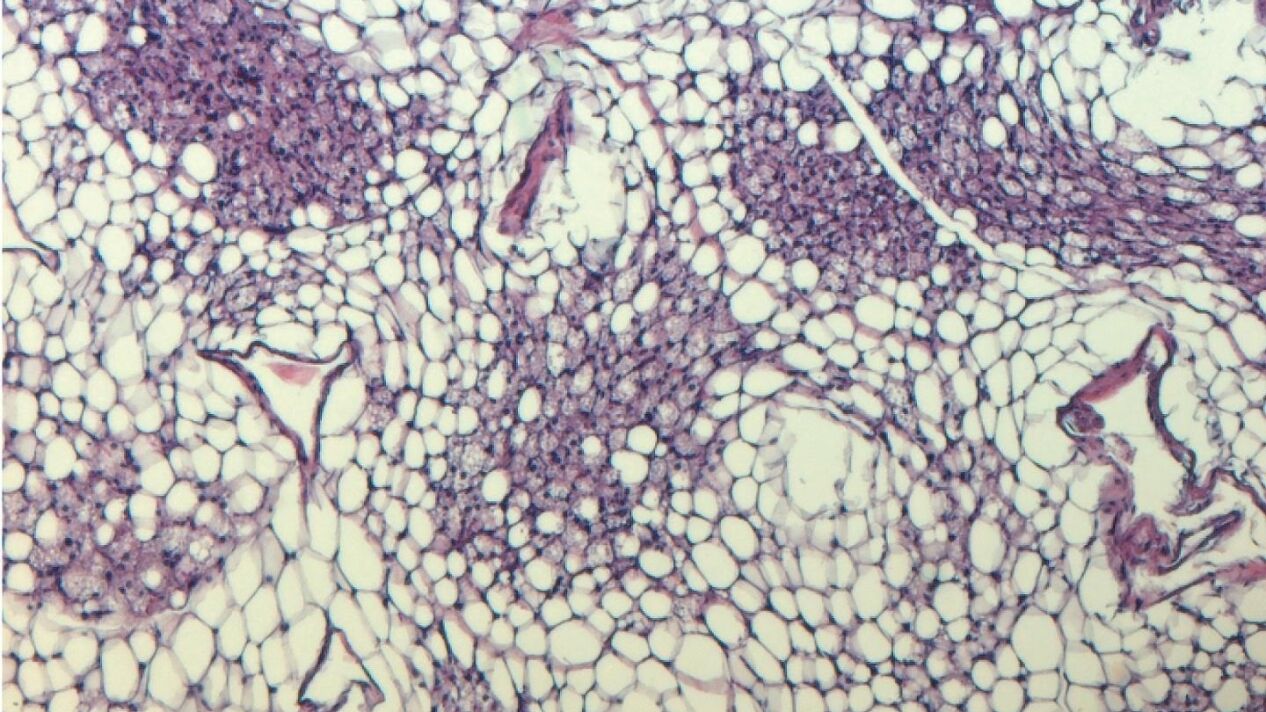

"Si un transportador de inosina es menos activo, los ratones se mantienen significativamente más delgados a pesar de una dieta alta en grasas", informa dicha agencia. Normalmente, las células grasas almacenan energía. Sin embargo, en las células de grasa marrón, la energía se disipa en forma de calor, por lo que la grasa marrón sirve de calentador biológico. Por ello, la mayoría de los mamíferos disponen de este mecanismo que en los humanos mantiene calientes a los recién nacidos; mientras que en los adultos, la activación de la grasa parda se correlaciona positivamente con la salud cardiometabólica.

"Hoy en día, sin embargo, estamos bien abrigados incluso en invierno. Así que los hornos propios de nuestro cuerpo ya casi no son necesarios. Al mismo tiempo, llevamos una dieta cada vez más densa en energía y también nos movemos mucho menos que nuestros antepasados. Estos tres factores son un veneno para las células de grasa marrón: Poco a poco dejan de funcionar y acaban muriendo. Por otra parte, el número de personas con sobrepeso severo en todo el mundo sigue aumentando. Por ello, grupos de investigación de todo el mundo buscan sustancias que estimulen la grasa parda y aumenten así la quema de grasas", afirma Alexander Pfeifer, uno de los responsables del trabajo.

Sin embargo, lo más interesante fue cómo las células de grasa parda intactas respondieron a la llamada de auxilio molecular: Se activaron por la inosina (o simplemente por las células moribundas de su entorno). Así, la inosina avivó el fuego en su interior. Las células de grasa blanca también se convirtieron en sus hermanas marrones. Los ratones alimentados con una dieta alta en energía y tratados al mismo tiempo con inosina se mantuvieron más delgados en comparación con los animales de control y quedaron protegidos de la diabetes.

El transportador de inosina parece desempeñar un papel importante en este contexto. Esta proteína de la membrana celular transporta la inosina al interior de la célula, reduciendo así la concentración extracelular. Por lo tanto, la inosina ya no puede ejercer su efecto promotor de la combustión. "Hay un fármaco que en realidad se desarrolló para los trastornos de la coagulación, pero que también inhibe el transportador de inosina. Administramos este fármaco a ratones y, como resultado, quemaron más energía", dice Pfeifer.